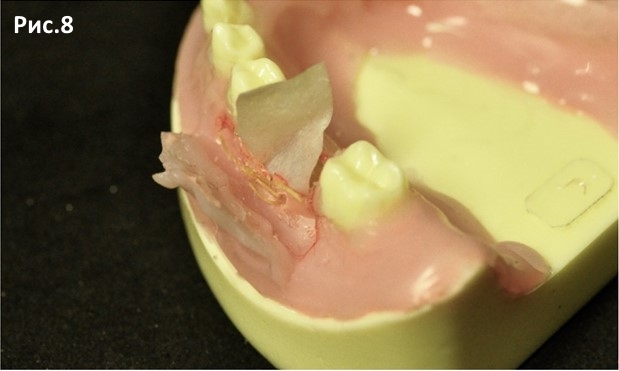

Подшитая мембрана. Рис.8